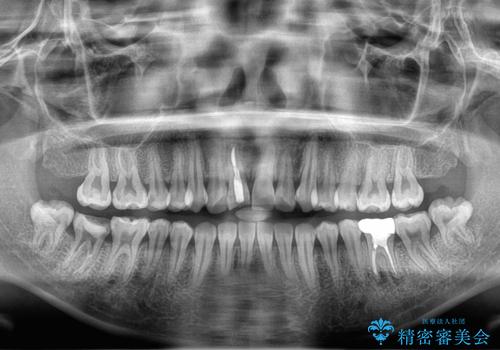

- セラミック矯正希望で来院された患者さんです。

歯周組織の状態が悪く、この状態ではきれいにかぶせものを入れることができないため、仮歯にかえてある程度見た目を改善した上で、歯周基本治療を進めることに。

歯肉の状態が改善できたら、セラミックに変えていく治療計画を立てました。

歯周組織がある程度改善されるまでに3か月ほどかかりました。

いざ型どりしていくというタイミングで、前歯の大きさが違いすぎるのが気になるとのことで歯周外科治療(アピカリ)にて歯肉のラインを整えることに。

歯肉の治りを待ったうえで(約8か月)、最終補綴することとなりました。